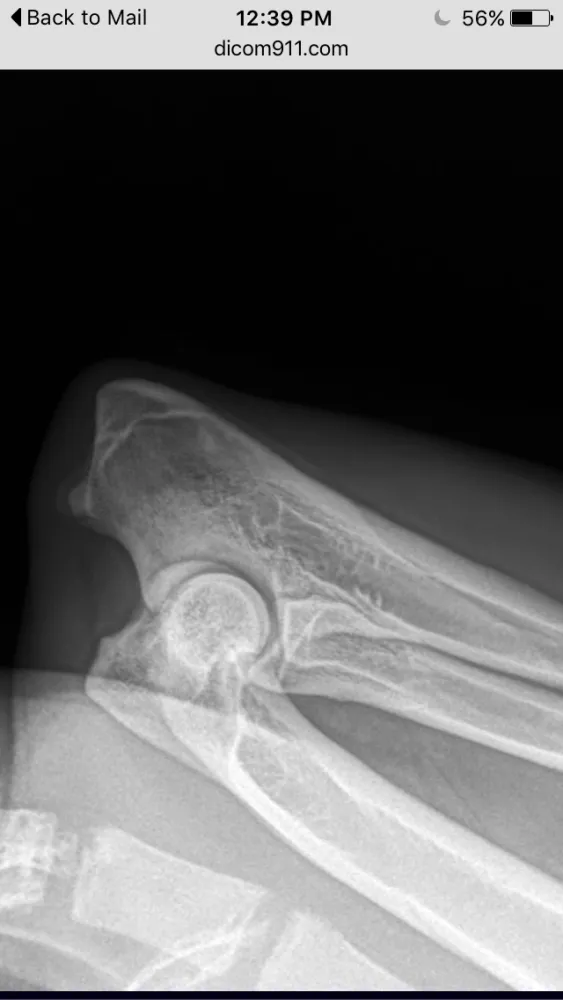

In December 2014, I purchased a german shepherd puppy from Tropisch German Shepherds. When my puppy was 8 months, he started limping and it continued for a few days so I brought him to my vet. The vet gave him anti-inflammatory pills and the limping went away after a few days. The limping came back about a month later and again, I went to my vet and she gave him anti-inflammatory pills and the limping went away after a few days. My vet told me that if the limping came back a third time, we would have to do an x-ray. The limping came back and about 2 months ago, my dog had the x-ray which revealed the beginning stages of hip dysplasia, panosteitis and arthritis. My vet told me these conditions are progressive and there is nothing I can do to prevent it. I am devastated and disgusted with this breeder. She is young, inexperienced and obviously doesn't care that she is breeding dogs with health problems and selling the puppies to people just for the money. I love my puppy and I am going to give him the best life I can possibly give him, but people need to know that Tropisch German Shepherds is dirty and they breed dogs with health problems. Please stay away from this breeder.